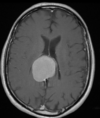

41

Meningioma do tubérculo da sela.

Meningioma Suprasselar realce homogêneo